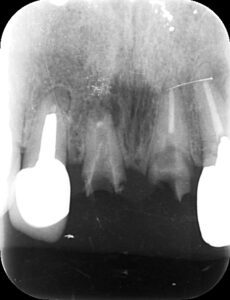

画像は転倒で差し歯が抜けて歯が割れてしまった場合です。

矢印部分の歯が欠けています。

レントゲンでも横に破折の線が入っているのが

わかります。